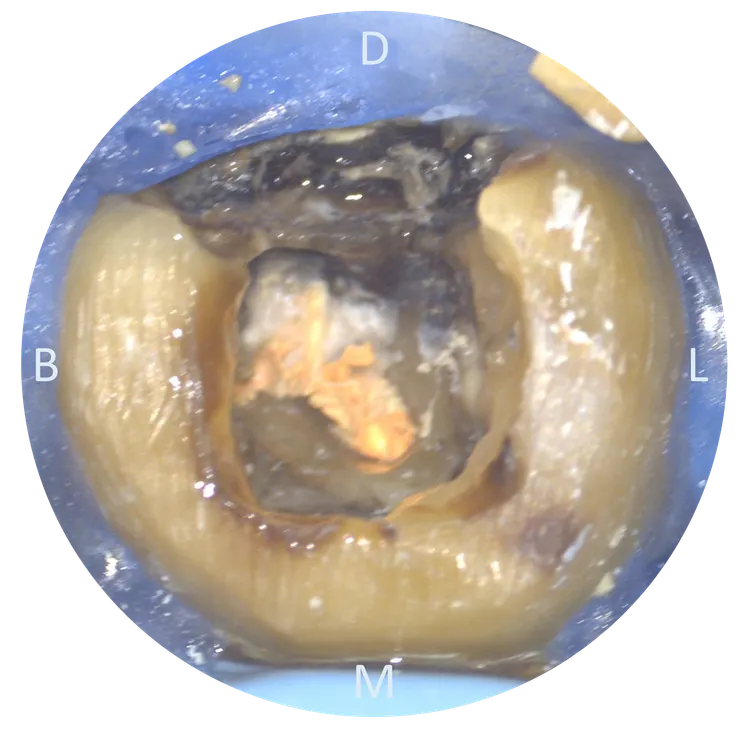

把 CBCT 的資訊記在腦中後,我們轉移到顯微鏡下來看看實際的情況:

可以看到用了五年的 temporary crown 下已經養出了一推 caries......

先把 caries 挖乾淨後再開始 retreat.

這次主要 focus 在箭頭所指的 ML canal.

把舊 GP 大致移除後,幸運地在根管壁上看到一個突兀的洞 (紅色箭頭所指),剛好就位於原本路徑 (粉紅色箭頭) 的 DB side !

拿起 file 瞄準那個洞督進去 ---

(這輕描淡寫的一句話,真要在張口度受限的 37 ML canal 中段做到,其實相當相當不容易......)

就找到了真正的 ML canal pathway !

然後就完成了 C&S 並且 RCF.